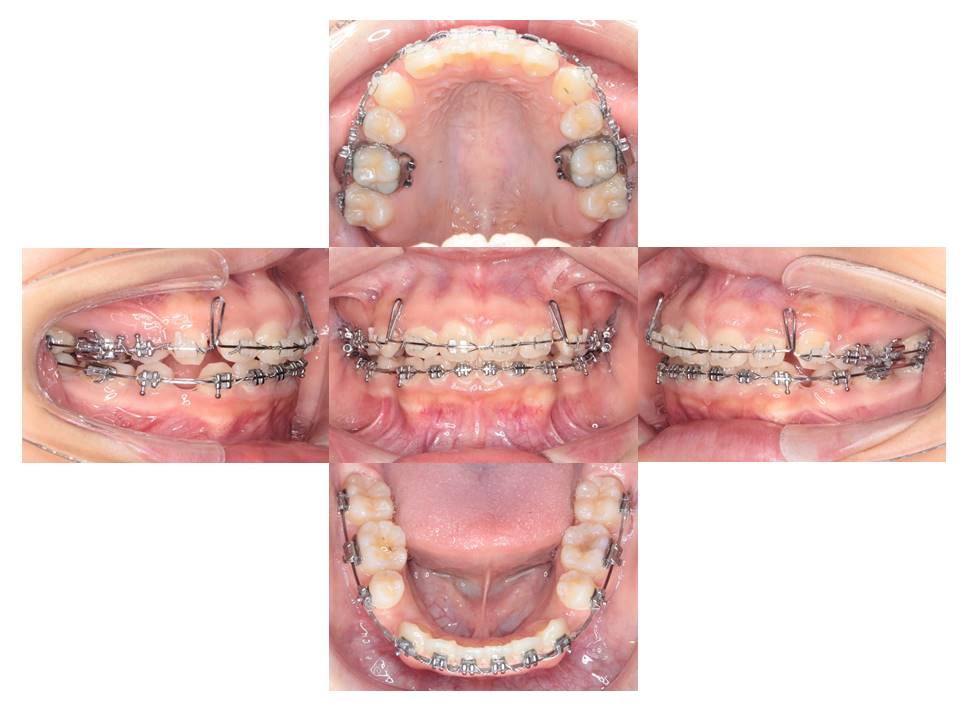

ワイヤー矯正にて治療中の口腔内(上下左右の計4本の抜歯をしています)